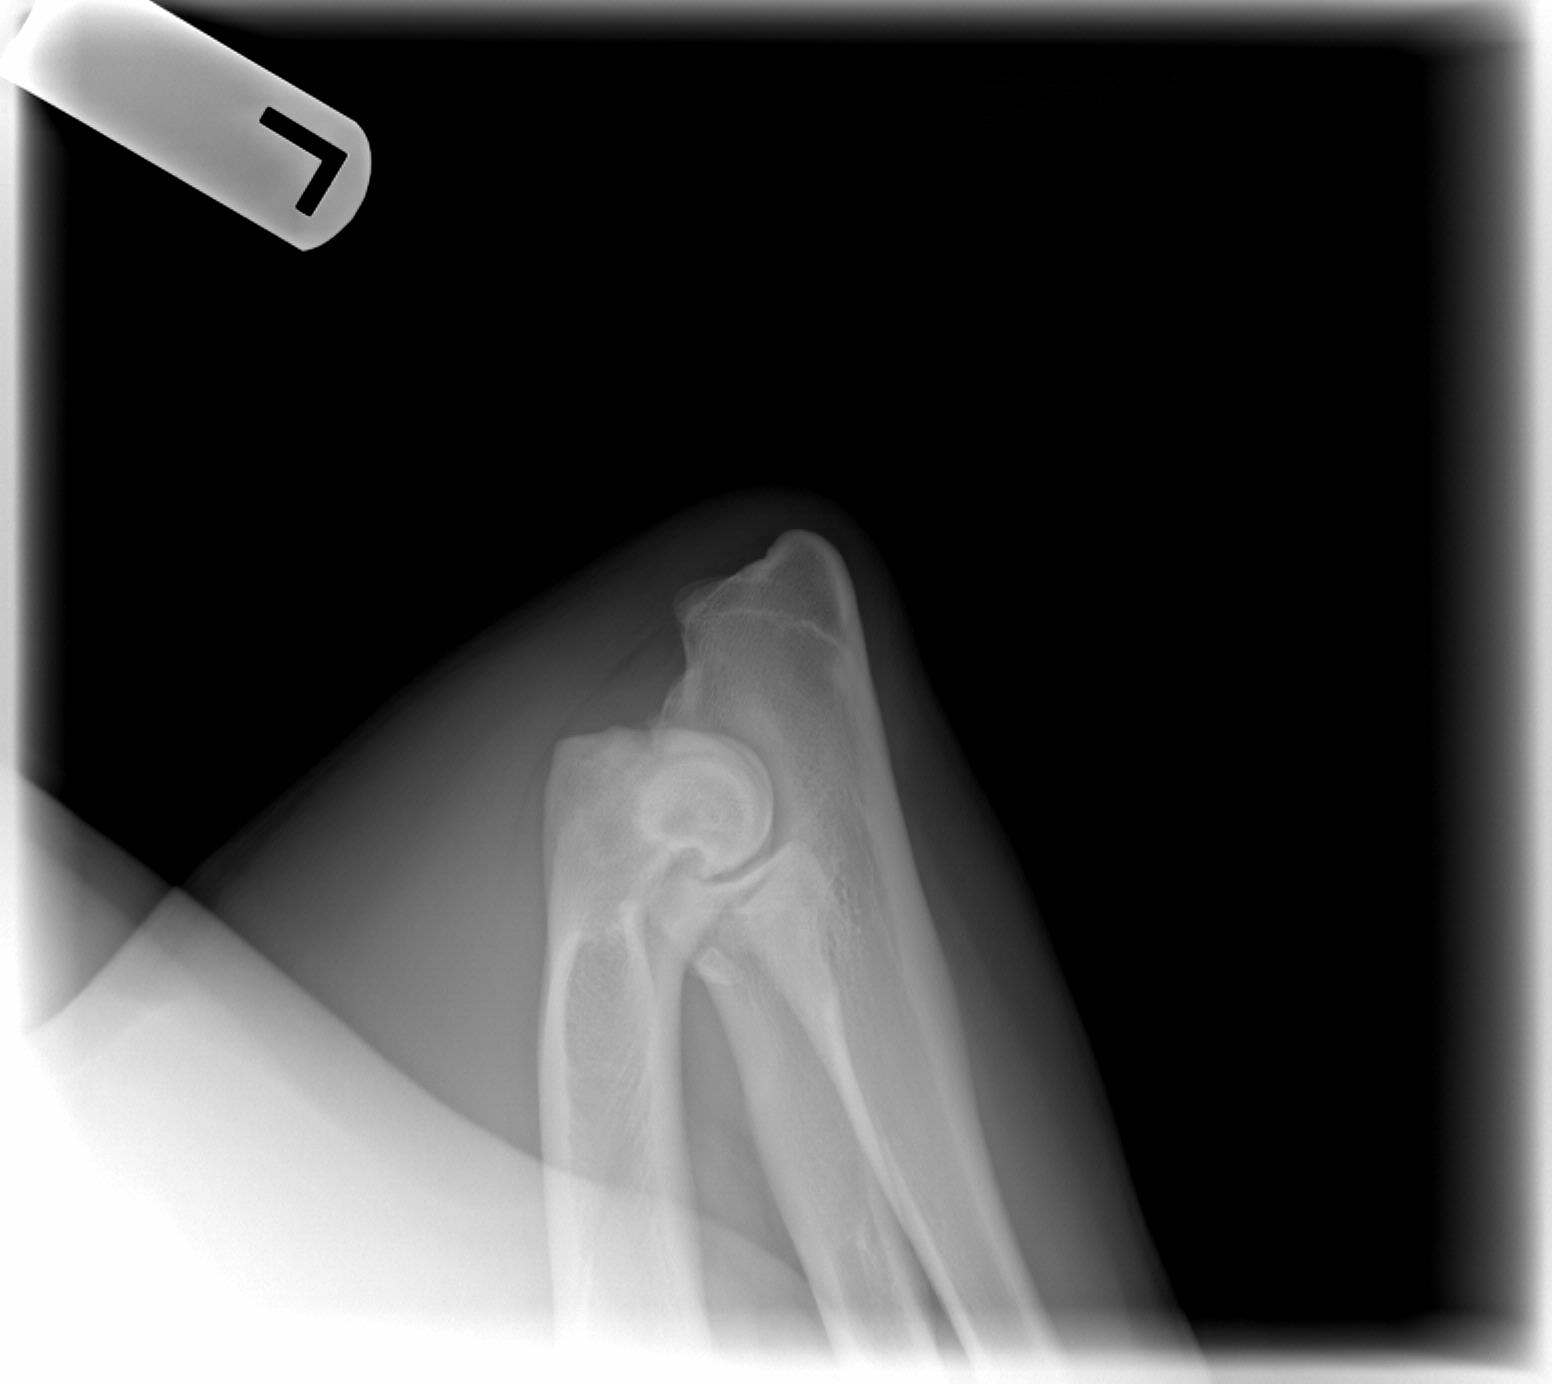

Barry's hips and elbows, taken on 1/7/08. My vet said he would be "shocked" if he did not get an Excellent but OFA gave them a Good. The third time they looked at them OFA changed one elbow from clear to Grade 1, however. We are disappointed. Both his littermates have gotten OFA Excellents, normal elbows, so that is nice. We'll try again for the perfect chocolate boy with Adam and Woody. :)